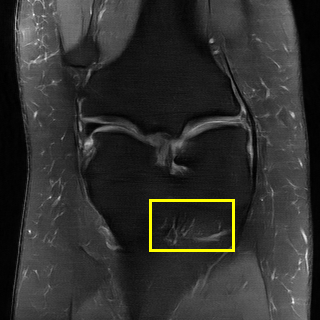

Edge preserving has always been a crucial concern in the design of reconstruction models. To improve the quality of reconstructed images and preserve image edges, some works suggested introducing edge priors in the original restoration problem to preserve image edges [4, 34]. However, they will suffer from complicated algorithm design and time-consuming training processes. Recently, some more efficient methods have been proposed to use edge maps as external guidance for image restoration. For example, Yang et al. [48] used off-the-shelf edge detectors to extract image edges from the degraded images. Fang et al. [12] predicted image edges by constructing an edge reconstruction network. Huang et al. [18] designed a novel dual discriminator GAN framework for solving fast multi-channel MRI, in which one GAN network is built for edge information enhancement. Inspired by these methods, we also consider introducing image edge prior as external guidance to MRI reconstruction since 1) image edges are prominent and distinguishable features in MRI (see Fig. 1), which can serve as a good guide to the model to recover high-frequency details; 2) the ground truth edges can be easily fetched via ordinary edge extraction operators, like Canny, Sobel, and Prewitt, which means that the edge maps can be learned in a data-driven manner. However, how to effectively utilize image edge priors to guide image reconstruction still remains a challenge. In some methods, edge information was simply concatenated with the input image and passed to the next stages. Though this is a simple way to utilize the edge priors, it may not give full play to the guiding role of the edge priors. Therefore, in this work, we want to explore a more efficient and effective mechanism to fully take advantage of image edge priors.

(a)

(b)

(c)

fastMRI is a large-scale MR dataset jointly established by Facebook AI Research and NYU Langone Health. It provides both knee and brain datasets for evaluation. In our work, we use the multi-coil knee dataset, which was acquired on three clinical 3T systems or one clinical 1.5T system using a 15-channel knee coil array. The dataset includes data from two pulse sequences, yielding coronal proton-density weighting with (PDFS) and without (PD) fat suppression. As is shown in Fig. 1, PD images usually contain more structural and prominent edge features than PDFS images, which suggests that it is more challenging to use edge guidance on PDFS datasets. Therefore, we explore the effectiveness of EAMRI on these two modalities. Following [13], for both PD and PDFS knee datasets, we separately filter out 227 volumes (8332 slices) for training and 24 volumes (1665 slices) for testing. The dataset is centrally cropped to .